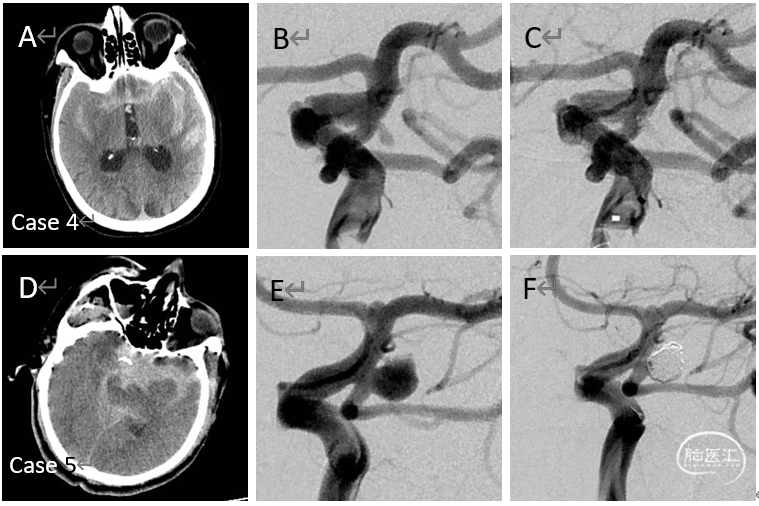

病例6-7

破裂的小脑前下动脉起始部动脉瘤

(Hunt-Hess 5级,Case 6)

破裂的左侧大脑中动脉分叉部动脉瘤

(Hunt-Hess 5级, Case 7)

急性期给予单纯栓塞,接着分别进行脑室外引流(Case6)和颅内血肿清除+去骨瓣减压术(Case7)